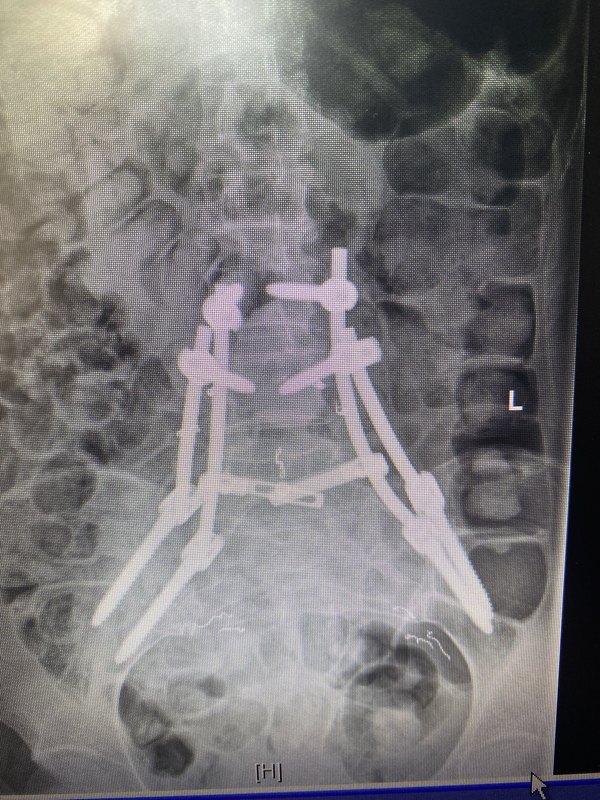

袁霆,國家骨科醫(yī)學(xué)中心主任醫(yī)師,上海六院骨科骨腫瘤科主任醫(yī)師,上海交通大學(xué)研究生導(dǎo)師一、骨盆腫瘤:隱藏在人體“核心區(qū)”的致命威脅骨盆是人體承上啟下的“核心區(qū)”,包裹著腸道、膀胱、子宮、血管和神經(jīng)等關(guān)鍵器官。然而,這個(gè)復(fù)雜的解剖結(jié)構(gòu)也讓它成為骨腫瘤的“高危地帶”。骨盆惡性腫瘤早期癥狀隱匿,患者常因輕微疼痛或排尿困難誤以為是痔瘡或關(guān)節(jié)炎,導(dǎo)致確診時(shí)腫瘤已長到拳頭大小,甚至壓迫器官,危及生命。更殘酷的是,傳統(tǒng)手術(shù)常需切除半側(cè)骨盆,患者術(shù)后可能面臨下肢癱瘓或終身掛尿袋的困境。即便能保肢,標(biāo)準(zhǔn)化的金屬假體也難以匹配復(fù)雜骨骼結(jié)構(gòu),術(shù)后關(guān)節(jié)僵硬、假體松動等問題頻發(fā)。二、3D打印技術(shù):從“私人訂制”到“與時(shí)間賽跑”過去十年,3D打印技術(shù)為骨盆腫瘤患者帶來了曙光。醫(yī)生可通過CT掃描數(shù)據(jù),打印出與患者骨骼完全匹配的鈦合金假體,實(shí)現(xiàn)“精準(zhǔn)替換”。但這項(xiàng)技術(shù)有個(gè)致命痛點(diǎn):從設(shè)計(jì)到假體送達(dá)醫(yī)院需3-4周。對惡性程度高的腫瘤來說,等待意味著癌細(xì)胞可能擴(kuò)散,假體尺寸也不再適用。一位醫(yī)生曾感慨:“眼睜睜看著患者的腫瘤在等待中瘋長,卻無能為力。”三、組配式假體:像“拼樂高”一樣拯救生命2021年,北京大學(xué)人民醫(yī)院郭衛(wèi)教授團(tuán)隊(duì)的一項(xiàng)發(fā)明改寫了游戲規(guī)則——3D打印鈦合金組配式人工半骨盆假體(GPS系統(tǒng))。這套假體由多個(gè)模塊組成,醫(yī)生可像“拼樂高”一樣,在術(shù)中根據(jù)實(shí)際切除范圍快速組裝,徹底告別漫長等待。這項(xiàng)技術(shù)有多強(qiáng)?時(shí)間殺手:術(shù)前無需定制,患者確診后可直接手術(shù),將治療周期從1個(gè)月壓縮至幾天。精準(zhǔn)適配:模塊化設(shè)計(jì)能靈活匹配不同切除范圍,甚至可調(diào)整角度,避免傳統(tǒng)假體“削足適履”的尷尬。功能升級:假體表面布滿微孔,促進(jìn)自體骨長入,遠(yuǎn)期穩(wěn)定性提升50%。四、技術(shù)背后的溫度:讓患者“有尊嚴(yán)地站立”醫(yī)學(xué)進(jìn)步的終極目標(biāo),不僅是延長生命,更是守護(hù)生活的尊嚴(yán)。傳統(tǒng)截肢手術(shù)雖能保命,卻讓患者陷入身心雙重創(chuàng)傷。而3D打印組配式假體的意義在于:保命更要保功能:患者術(shù)后可站立、行走,甚至恢復(fù)運(yùn)動。降低醫(yī)療成本:國產(chǎn)假體打破進(jìn)口壟斷,價(jià)格僅為進(jìn)口產(chǎn)品的1/3。推動技術(shù)普惠:全國已有十多家醫(yī)院開展此類手術(shù),更多患者無需跨省求醫(yī)。正如一位患者家屬所說:“以前覺得能活下來就是萬幸,現(xiàn)在居然還能正常生活——這是醫(yī)學(xué)給的奇跡?!蔽?、未來展望:3D打印如何改寫癌癥治療?當(dāng)前,3D打印技術(shù)已從骨骼重建延伸到血管、軟骨甚至器官打印??茖W(xué)家正在探索“生物活性假體”——植入后能釋放抗癌藥物,或攜帶干細(xì)胞促進(jìn)組織再生。也許未來某天,癌癥治療將像更換汽車零件一樣精準(zhǔn)可控。參考文獻(xiàn)GuoW,etal.?JBoneJointSurgAm.2020;102(21):e120.(郭衛(wèi)團(tuán)隊(duì)3D打印假體臨床研究)LiC,etal.?OrthopSurg.2021;13(5):1567-1574.(骨盆腫瘤多學(xué)科治療模式)DadiaS,etal.?FrontBioengBiotechnol.2022;10:901234.(生物活性植入物研究進(jìn)展)作者心語:作為一名醫(yī)生,最欣慰的時(shí)刻莫過于看到患者重新站起來的笑容。醫(yī)學(xué)技術(shù)的每一小步,都是患者生命質(zhì)量的一大步。愿科學(xué)之光照亮更多絕望中的家庭,讓“不可能”變?yōu)椤翱赡堋薄?/p>

骨盆腫瘤是診斷和治療的難題。由于骨盆的解剖位置較深,臨床表現(xiàn)較晚,骨盆腫瘤往往較大,位于骨盆內(nèi)臟和重要的神經(jīng)血管結(jié)構(gòu)附近。骨盆腫瘤的手術(shù)治療是指各種骨科腫瘤條件。一般來說,保肢的骨盆切除術(shù),而不是半側(cè)骨盆切除術(shù),同側(cè)肢體截肢時(shí),可以考慮保留一個(gè)功能性肢體而不損害手術(shù)邊緣。骨盆切除和重建有多種選擇,選擇取決于腫瘤組織學(xué)、解剖部位和范圍。骨盆腫瘤的手術(shù)方法和重建方法的選擇需要對骨盆解剖學(xué)有充分的了解,并且要仔細(xì)檢查解剖范圍。手術(shù)計(jì)劃必須在可接受的功能結(jié)果和可接受的發(fā)病率之間取得平衡。在這篇綜述中,我們描述了不同類型的骨盆切除技術(shù),以及術(shù)前影像在確定骨盆腫瘤的解剖范圍和隨后的手術(shù)計(jì)劃中的重要作用。大約15-20% 的原發(fā)性骨腫瘤和大約5% 的原發(fā)性軟組織肉瘤發(fā)生在骨盆。骨盆腫瘤與四肢腫瘤有許多重疊的特征,包括相似的組織學(xué)光譜,雖然有關(guān)鍵的區(qū)別。與周圍骨骼的腫瘤相反,骨盆的大多數(shù)骨腫瘤是惡性的,其中軟骨肉瘤、尤文肉瘤和骨肉瘤是三種最常見的原發(fā)性骨腫瘤。在40歲以上的患者中,骨髓瘤和轉(zhuǎn)移性疾病也常見于骨盆。除了原發(fā)性骨性惡性腫瘤外,某些良性和偶爾侵襲性的腫瘤如骨巨細(xì)胞瘤、動脈瘤樣骨囊腫和脊索瘤也發(fā)生于骨盆。骨盆骨腫瘤是一個(gè)挑戰(zhàn),檢測,由于其深部位置相比,腫瘤位于外周骨骼。因此,這些腫瘤在最終診斷時(shí)通常表現(xiàn)為較大的腫瘤。較大的尺寸與骨盆復(fù)雜的軟組織和骨性解剖結(jié)構(gòu)共同創(chuàng)造了技術(shù)上具有挑戰(zhàn)性的手術(shù)場景。手術(shù)治療骨盆腫瘤,包括半切除術(shù),在技術(shù)上是艱巨的手術(shù)程序,通常是為了處理惡性和一些良性骨盆腫瘤。有時(shí),一個(gè)孤立的轉(zhuǎn)移性病灶,嚴(yán)重的創(chuàng)傷或頑固性感染可能需要這樣一個(gè)廣泛的手術(shù)。因此,潛在腫瘤的生物學(xué)行為決定了腫瘤的侵襲程度或手術(shù)切緣,以及術(shù)前輔助放療和/或化療的必要性。放射科醫(yī)生在骨盆腫瘤患者的治療中起著重要作用,因?yàn)闇?zhǔn)確評估腫瘤的解剖部位和范圍對于確定手術(shù)的可行性至關(guān)重要。只有在不影響腫瘤復(fù)發(fā)所需的足夠手術(shù)切緣的情況下,能夠維持功能性肢體的情況下,才能考慮不截肢的骨盆切除術(shù)。一般來說,在考慮保肢骨盆手術(shù)時(shí)有三個(gè)關(guān)鍵的解剖學(xué)區(qū)域需要評估: 股神經(jīng)血管束、坐骨神經(jīng)和髖臼。如果三個(gè)關(guān)鍵結(jié)構(gòu)中的兩個(gè)可以幸免,患者通常是保肢手術(shù)的候選者。如果這些因素中的兩個(gè)需要犧牲,病人最好采取截肢手術(shù)。在這篇綜述文章中,我們描述了不同類型的骨盆切除技術(shù),并闡明了術(shù)前成像在確定骨盆腫瘤的解剖位置和范圍以便手術(shù)計(jì)劃中的重要作用。骨盆腫瘤的手術(shù)治療骨盆切除術(shù)的主要目標(biāo)是使用提供最低復(fù)發(fā)風(fēng)險(xiǎn)的技術(shù)完全切除骨腫瘤。同時(shí)保留同側(cè)肢體功能結(jié)果良好是理想的,但保留肢體不應(yīng)以增加復(fù)發(fā)為代價(jià)。根據(jù)腫瘤邊緣與腫瘤及腫瘤周圍水腫或強(qiáng)化(“反應(yīng)區(qū)”)的關(guān)系,有四種類型的手術(shù)切緣: 腫瘤內(nèi)、邊緣、擴(kuò)大切除。原發(fā)性骨肉瘤需要邊緣陰性切除,最好在擴(kuò)大或根治性邊緣切除。對于較寬的切緣,正常組織的袖帶仍然存在,但袖帶的大小或腫瘤與正常組織之間必要的最小距離以減少復(fù)發(fā)是有些爭議的。根治性切除包括切除整個(gè)骨盆腔,在某些情況下,腫瘤延伸到骶骨,需要進(jìn)行部分骶骨切除以達(dá)到一個(gè)陰性切緣。保肢骨盆手術(shù)Enneking 描述了保肢骨盆切除分類方案。I 型切除包括髂翼任何部分的切除。這個(gè)區(qū)域的切除有良好的功能結(jié)果。保持骨盆環(huán)連續(xù)性的髂骨翼部分切除不需要重建。完全切除髂骨會造成骶骨和髖臼之間的不連續(xù),導(dǎo)致殘余的半髖關(guān)節(jié)向上移位,因此需要重建以防止這種并發(fā)癥。因此,放射科醫(yī)生有必要評估髂骨腫瘤與骶髂關(guān)節(jié)的接近程度。II 型切除是為了髖臼周圍骨骼病變。根據(jù)定義,髖關(guān)節(jié)參與了這個(gè)過程,因此,這些切除是最具挑戰(zhàn)性的重建。不良結(jié)果和并發(fā)癥繼發(fā)于這些切除可以是顯著的。重建通常是首選的這些情況下,并存在許多選擇涉及各種裝置和假體。沒有重建導(dǎo)致連股髖關(guān)節(jié)和假關(guān)節(jié)也是一個(gè)選擇。病變的坐骨神經(jīng)系統(tǒng)區(qū)域是治療與 III 型切除。這些切除與良好的結(jié)果,因?yàn)轶y臼是幸免的。雖然骨重建是不必要的,軟組織重建通常是為了防止通過閉孔孔對盆腔內(nèi)臟器進(jìn)行疝出。放射科醫(yī)生必須仔細(xì)評估坐骨腫瘤到恥骨聯(lián)合的距離,因?yàn)樗ㄟ^完成骨盆環(huán)和固定腹直肌腱膜來提供骨盆固有的穩(wěn)定性。根據(jù)腫瘤的部位,III 型骨盆切除的患者可能會出現(xiàn)內(nèi)收肌或腘繩肌無力。當(dāng)腫瘤跨越骨盆的一個(gè)以上區(qū)域時(shí),切除類型是合并的。例如,i/II 型切除術(shù)同時(shí)涉及髂翼和髖臼。I/II/III 型骨盆切除術(shù)是真正的半骨盆切除術(shù)。骶骨受累需要行 IV 型切除術(shù)。部分骶骨切除術(shù)適用于 S2以下的腫瘤,不需要重建。同樣,放射科醫(yī)師必須仔細(xì)評估骶骨腫瘤的外側(cè)范圍,并檢查骶髂關(guān)節(jié)。不延伸至骶骨關(guān)節(jié)的骶骨外側(cè)腫瘤可以采用部分矢狀骶骨切除術(shù)治療,而向骶骨外側(cè)腫瘤延伸至骶骨關(guān)節(jié),除了部分矢狀骶骨切除術(shù)(i 型和 IV 型聯(lián)合切除術(shù))外,還需要有限度的髂后骨盆切除術(shù)。中線骶骨腫瘤(S2段的顱側(cè)和尾側(cè))需要橫行骶骨切除術(shù)(圖7)。當(dāng)骶骨腫瘤累及更多的骶骨近端部分并向前延伸時(shí),應(yīng)行全骶骨切除術(shù)。骶骨遠(yuǎn)端部分切除很少需要重建,但對于骶骨完全切除或骶1和骶2部分切除則需要重建。此外,IV 型骨盆切除可根據(jù)骶骨受累情況進(jìn)行分類: 累及同側(cè)骶骨翼(IVa 亞型) ,累及同側(cè)骶骨孔(IVb 亞型) ,累及對側(cè)骶骨孔(IVc 亞型) ,最后累及整個(gè)骶骨(IVd 亞型)[23]。主要的脊椎骨盆切除可以根據(jù)腰骶部切除的范圍,基于 S1以上的脊柱腫瘤的解剖學(xué)范圍和同時(shí)需要半骨盆切除(橫向范圍超過骶髂關(guān)節(jié))來分類。截肢術(shù)如果腫瘤需要切除半個(gè)骨盆,則進(jìn)行半骨盆切除術(shù)。術(shù)語“半骨盆切除術(shù)”是指通過 SI 關(guān)節(jié)的截肢術(shù)。如果腫瘤能夠保留下肢的主要神經(jīng)血管結(jié)構(gòu)(股動脈、靜脈、神經(jīng)以及外髂動脈和靜脈)和功能性肢體,而又不影響將腫瘤復(fù)發(fā)風(fēng)險(xiǎn)降到最低所需的廣泛切除,則可以進(jìn)行保肢性骨盆切除術(shù)。術(shù)語“內(nèi)半骨盆切除術(shù)”是一個(gè)誤稱,因?yàn)樗且环N骨盆切除術(shù)而不是截肢術(shù)。然而,這個(gè)術(shù)語在文獻(xiàn)中通常被用來描述一個(gè)局部切除包括全部或部分半側(cè)同時(shí)保留同側(cè)下肢。隨著神經(jīng)血管重建技術(shù)的進(jìn)步,95% 的患者可以采用保肢骨盆切除術(shù)而不是半側(cè)骨盆切除術(shù)和同側(cè)肢體截肢術(shù)[24]。如果有明顯的神經(jīng)血管受累、腫瘤內(nèi)感染或預(yù)期功能預(yù)后不良,則可能需要截肢。放射科醫(yī)生必須仔細(xì)評估骨盆腫瘤與腰骶神經(jīng)叢/坐骨神經(jīng)、股神經(jīng)血管束和髖關(guān)節(jié)的接近程度。如果有兩個(gè)或兩個(gè)以上的解剖結(jié)構(gòu)需要切除,殘肢基本上是無功能的,可能需要進(jìn)行外部半髖切除術(shù)而不是保肢手術(shù)。當(dāng)半側(cè)腰椎、部分或整個(gè)骶骨以及部分下脊柱連同 LS 叢一起切除時(shí),不論是否切除髖關(guān)節(jié),都需要進(jìn)行擴(kuò)大的半側(cè)腰椎切除術(shù)。骨盆部腫瘤術(shù)前局部分期的影像學(xué)對策術(shù)前磁共振成像用于評估盆腔腫瘤的范圍,并通過確定腫瘤與鄰近神經(jīng)血管結(jié)構(gòu)的關(guān)系來計(jì)劃手術(shù)切緣。這使外科醫(yī)生可以確定是否會嘗試重建,以及是否需要其他外科附屬??频膮⑴c。手術(shù)計(jì)劃的一個(gè)重要考慮因素是能否達(dá)到陰性的手術(shù)切緣。邊緣組織的質(zhì)量(假囊相對于正常組織的袖帶)與腫瘤和未受累組織之間的距離一樣重要。骨盆切除要考慮的三個(gè)主要結(jié)構(gòu)包括 LS 神經(jīng)叢/坐骨神經(jīng)、股神經(jīng)血管束和髖關(guān)節(jié)/髖臼周圍區(qū)。正如已經(jīng)討論過的,如果這些結(jié)構(gòu)中的任何兩個(gè)必須切除以達(dá)到負(fù)的邊緣,半骨盆切除術(shù)應(yīng)該被認(rèn)為是肢體功能嚴(yán)重受損。影像學(xué)X線對所有骨腫瘤患者的調(diào)查,無論是良性或惡性,都從影像學(xué)開始。影像學(xué)的主要作用包括評價(jià)骨腫瘤角色塑造內(nèi)的基質(zhì)礦化模式(軟骨樣與骨樣) ,而不是評價(jià)其程度(最好由磁共振成像進(jìn)行)。它還可以幫助我們了解骨質(zhì)脫礦的總體程度以及病理性骨折和骨量丟失的風(fēng)險(xiǎn),這些因素可能會對重建策略產(chǎn)生影響。CT對于骨腫瘤的評估,CT X射線計(jì)算機(jī)斷層成像比軟組織腫塊更有用。三維(3D)容積提供 CT 成像可用于外科醫(yī)生規(guī)劃骨盆腫瘤切除。此外,CT 和 MRI 的融合也可以提供關(guān)于骨盆骨腫瘤的骨性和骨外或軟組織成分的有用信息。與 x 線攝影相似,CT 詳細(xì)記錄了腫瘤的位置以及是否存在骨或軟骨樣鈣化和皮質(zhì)受累。由于這個(gè)原因,在評價(jià)骨樣骨瘤、骨膜反應(yīng)、基質(zhì)礦化和髂骨等扁平骨病變時(shí),有時(shí)優(yōu)于 MRI。對比增強(qiáng) CT 檢查,尤其是 CT 血管造影,可以幫助確定血管受累,這對于計(jì)劃復(fù)雜的切除手術(shù)至關(guān)重要,但是與非增強(qiáng)的圖像相比,其優(yōu)勢很小。在許多情況下,CT 最有用的應(yīng)用是指導(dǎo)活檢。一個(gè)準(zhǔn)確和適當(dāng)?shù)亩ㄎ换顧z可以是一個(gè)整體步驟的治療計(jì)劃為許多腫瘤?;罱M織檢查應(yīng)該在所有其他初步成像完成后進(jìn)行,因?yàn)榕c活檢有關(guān)的水腫或出血可能會影響圖像。活檢軌跡的規(guī)劃應(yīng)與手術(shù)團(tuán)隊(duì)協(xié)商,避免在活檢道的股直肌和臀大肌肌肉,因?yàn)樵S多腫瘤將需要切除該軌跡作為最終外科處理的一部分[27]。最后,CT 也是評估腫瘤與盆腔臟器,尤其是腸道的關(guān)系的有效手段,尤其是大多數(shù)外科醫(yī)生可能更愿意為此目的使用 CT 而不是 MRI 。在不久的將來,3D 打印技術(shù)也可能在骨盆腫瘤切除和重建的術(shù)前規(guī)劃中發(fā)揮更重要的作用。MRI雖然 MRI 和 CT 在原發(fā)性骨腫瘤的角色塑造診斷中是等價(jià)的,但是 MRI 對于確定骨盆腫瘤的范圍是不可或缺的。MRI 在確定皮質(zhì)骨和關(guān)節(jié)受累方面相當(dāng)于 CT,在確定骨內(nèi)腫瘤長度、骨外延伸和神經(jīng)血管束受累方面優(yōu)于 CT,因此,MRI 應(yīng)用于局部分期和手術(shù)計(jì)劃。多平面 t1加權(quán)自旋回波或至少兩個(gè)平面的快速自旋回波序列是最有用的骨盆骨腫瘤的局部分期由于復(fù)雜的骨盆骨解剖。T1加權(quán)序列提供關(guān)于解剖位置和參與的髖關(guān)節(jié)以及 SI 關(guān)節(jié)的信息。應(yīng)性周圍性骨髓水腫和惡性病變的擴(kuò)展。最后,彌散加權(quán)成像(DWI) ,一種定量的,非對比度的 MRI 序列,是一個(gè)有用的武器組成部分,可以有助于骨盆腫瘤的角色塑造,作為非侵襲性的對侵襲性的和治療的反應(yīng),但是對于評估病變的解剖范圍沒有什么用處。病變的邊緣有時(shí)很難與鄰近的周圍性骨髓水腫或軸性骨骼中的致密紅骨髓反應(yīng)區(qū)(特別是年輕患者)區(qū)分開來。因此,先進(jìn)的 MRI 序列,如化學(xué)位移成像和擴(kuò)散加權(quán)成像可能是有用的。為此,通過在骨髓周圍信號異常的相位圖和相位圖上繪制感興趣區(qū)域(ROI) ,對感興趣區(qū)域進(jìn)行定量分析。在1.5 t 和3.0 t 的同相和反相圖像中,信號丟失率分別大于20% 和15% ,可用于區(qū)分非骨髓替代性信號異常(如周圍水腫的顯微脂肪區(qū))和骨髓替代性腫瘤(無顯微脂肪的良性或惡性骨腫瘤)。此外,動態(tài)增強(qiáng) MRI 也有助于區(qū)分反。除了骨盆骨腫瘤的解剖學(xué)范圍外,檢測跳躍性病變也很重要,跳躍性病變最常與骨肉瘤相關(guān)。跳躍性病變是指在同一骨內(nèi)(或在軟組織肉瘤環(huán)境中的間隔)同時(shí)出現(xiàn)的額外腫瘤病灶,在組織學(xué)上與原發(fā)腫瘤分離,跳過病變有重要的手術(shù)和預(yù)后影響。術(shù)前影像學(xué)分析結(jié)合上述討論的方式,放射科醫(yī)生必須準(zhǔn)確地描述骨盆骨腫瘤的解剖位置和范圍,特別是累及 LS 神經(jīng)叢/坐骨神經(jīng)、股神經(jīng)血管束和髖關(guān)節(jié)的情況,以便手術(shù)團(tuán)隊(duì)制定切除計(jì)劃。至關(guān)重要的是,病人接受后續(xù)成像任何新輔助治療手術(shù)前,重新界定的范圍和評估治療反應(yīng)。為了評估神經(jīng)血管包裹或基臺,軸面通常是最有用的,因?yàn)樗軌蛟u估神經(jīng)血管束周圍的脂肪。雖然目前還沒有關(guān)于 MRI 區(qū)分基牙與神經(jīng)血管束包裹的準(zhǔn)確性的數(shù)據(jù),但在我們的實(shí)踐中,我們傾向于使用神經(jīng)血管束周圍脂肪的部分或完全模糊和受影響神經(jīng)內(nèi)部強(qiáng)化的神經(jīng)內(nèi)部結(jié)構(gòu)變形,以及骨骼肌去神經(jīng)支配作為神經(jīng)受累的指標(biāo)。此外,髖關(guān)節(jié)受累是至關(guān)重要的,因?yàn)樗枰P(guān)節(jié)外切除。關(guān)節(jié)內(nèi)腫塊的存在或關(guān)節(jié)內(nèi)脂肪的模糊和病理性骨折可作為關(guān)節(jié)污染的標(biāo)志物坐骨神經(jīng):通過骨盆的軸向解剖(中間加權(quán)或T1加權(quán)序列,無脂肪抑制)和流體敏感序列(T2加權(quán)脂肪抑制(FS)或短τ反轉(zhuǎn)恢復(fù)(STIR)序列)的結(jié)合,實(shí)現(xiàn)了最小二乘神經(jīng)叢和坐骨神經(jīng)路徑的最佳可視化。正常、健康的神經(jīng)在解剖圖像上與骨骼肌呈等信號,在T2加權(quán)脂肪抑制上與骨骼肌呈等信號或稍高信號,在靜脈注射造影劑后不增強(qiáng)。用于檢測神經(jīng)叢/坐骨神經(jīng)惡性病變的有用影像學(xué)特征包括神經(jīng)周圍脂肪間隙消失、周圍包裹、結(jié)節(jié)狀或球狀增大,在T2加權(quán)脂肪抑制信號升高、結(jié)構(gòu)扭曲和對比劑給藥后內(nèi)部增強(qiáng)。它也有助于尋找骨骼肌失神經(jīng)的跡象,如水腫樣信號、脂肪替代和神經(jīng)受累區(qū)域遠(yuǎn)端的神經(jīng)支配肌肉萎縮。在腫瘤涉及骶骨、髖臼后部、骨盆邊緣和坐骨大孔的情況下,應(yīng)特別注意腰骶叢和坐骨神經(jīng)。如果腰骶骨軀干能幸免,首選保肢手術(shù)。STIR序列:(核磁共振檢查序列中,有個(gè)stir序列,是一個(gè)特殊的序列,又叫脂肪抑制序列。脂肪或者病灶中存在脂肪成分在核磁共振上t1表現(xiàn)為高信號,因?yàn)榇蟛糠值牟≡钤趖1都是低信號,所以可以通過t1高信號初步判斷病灶性質(zhì)。這個(gè)時(shí)候可以加做一個(gè)stir序列,在這個(gè)序列上出現(xiàn)高信號說明是脂肪或者是含有脂肪的病灶,對診斷有決定性的意義。)股神經(jīng)血管束股動脈特征性地位于前上髂嵴之間髂腰肌肌腱交界處是髂腰肌和恥骨結(jié)節(jié)之間唯一的結(jié)構(gòu)血管和髖關(guān)節(jié)囊,因此,髖臼周圍腫瘤累及髖關(guān)節(jié)應(yīng)該仔細(xì)評估股神經(jīng)血管受累神經(jīng)最好使用核磁共振檢查,最好在軸面信號強(qiáng)度,神經(jīng)結(jié)構(gòu),以及增強(qiáng)股神經(jīng)可提示神經(jīng)受累。骨骼肌失神經(jīng)支配的跡象髂腰肌內(nèi)的骨盆受累于股神經(jīng)。任何軟組織病變涉及髂骨需要特別注意股骨神經(jīng)。骨盆病變血管受累的詳細(xì)特征至關(guān)重要,因?yàn)檠苤亟ǖ娘@著進(jìn)展允許更頻繁的肢體挽救手術(shù)干預(yù)。這最好用核磁共振來完成。據(jù)報(bào)道,彩色雙功能超聲、計(jì)算機(jī)斷層掃描和正規(guī)血管造影可用于描述軟組織肉瘤對血管系統(tǒng)的侵犯,盡管磁共振成像被認(rèn)為是金標(biāo)準(zhǔn),可以最佳地評估腫瘤血管平面的血管受累情況。正常血管周圍脂肪邊緣的缺失構(gòu)成血管受累。血管受累的分類范圍從第一類到第三類,允許臨床小組適當(dāng)?shù)赜?jì)劃其重建。ⅰ型血管受累表明動脈和靜脈均被包裹、附著或浸潤。ⅱ型病變描述的是僅影響動脈的病變,而ⅲ型病變僅影響靜脈。ⅳ型病變表明沒有血管受累,不需要血管重建。髖關(guān)節(jié)髖臼周圍骨盆腫瘤延伸至髖關(guān)節(jié)對切除和重建有巨大影響,因?yàn)轶y關(guān)節(jié)需要進(jìn)行功能性治療。在大面積骨丟失的情況下,髖關(guān)節(jié)的外科重建是非常具有挑戰(zhàn)性的,并且經(jīng)常伴隨著諸如感染和功能低下等并發(fā)癥的增加。在某些情況下,半骨盆切除可能優(yōu)于保留肢體的骨盆切除。放射科醫(yī)師必須準(zhǔn)確描述腫瘤的范圍,特別是髖關(guān)節(jié)的受累情況。髖關(guān)節(jié)解剖結(jié)構(gòu)復(fù)雜,15%的病例與相鄰的髂腰肌囊相鄰。髂腰肌囊的擴(kuò)張不應(yīng)被誤認(rèn)為是腫塊的骨外延伸。髖關(guān)節(jié)骨結(jié)構(gòu)的研究應(yīng)該從錐形和居中的x光片開始。CT是評估軟骨下板皮質(zhì)破壞的最佳方法,而MRI是評估髖關(guān)節(jié)腫瘤關(guān)節(jié)內(nèi)擴(kuò)展的首選研究。有用的影像學(xué)發(fā)現(xiàn)包括腫瘤延伸到關(guān)節(jié)腔內(nèi)的直接可視化,滑膜內(nèi)脂肪的模糊,以及髖臼周圍骨病變延伸到髖關(guān)節(jié)的病理性骨折。骶髂關(guān)節(jié)骨盆骨腫瘤可以通過骶髂關(guān)節(jié)延伸到骶骨。很少有文獻(xiàn)描述影像學(xué)在檢測骨盆腫瘤關(guān)節(jié)內(nèi)延伸至骶髂關(guān)節(jié)的準(zhǔn)確性。以組織學(xué)為金標(biāo)準(zhǔn),磁共振成像對骶骨浸潤的敏感性為100%,特異性為92%,陽性預(yù)測值為83%,骶骨浸潤被定義為骶髂關(guān)節(jié)軟骨或骨破壞或磁共振成像上存在從骨盆延伸到骶骨的異常信號。在后一項(xiàng)研究中,假陽性結(jié)果是由于瘤周反應(yīng)性水腫和紅骨髓。因此,在t1加權(quán)序列上與髂骨腫瘤相鄰的骶骨外側(cè)骨髓置換是一個(gè)有用的影像學(xué)特征。在我們的實(shí)踐中,我們使用非對比T1加權(quán)序列、化學(xué)位移成像和對比后磁共振成像序列的組合來確定硅關(guān)節(jié)的受累情況。侵犯骶髂關(guān)節(jié)需要修改手術(shù)計(jì)劃,包括更復(fù)雜的脊柱切除和重建。此外,骶骨骨髓置換相對于神經(jīng)孔的范圍有助于確定截骨部位(包括骶骨翼、骶骨中線和對側(cè)骶骨或髂骨翼)以及是否需要結(jié)扎同側(cè)或雙側(cè)骶神經(jīng)根。盆腔臟器最后,重要的是評估骨盆內(nèi)骨腫瘤的延伸和骨盆內(nèi)臟的受累,如胃腸道和泌尿生殖道,因?yàn)檫@改變了手術(shù)計(jì)劃,可能需要在確定的手術(shù)治療中有額外的手術(shù)小組在場。大的骨盆骨腫瘤與鄰近的臟器非常接近,可能需要對鄰近的器官如輸尿管、膀胱、直腸/結(jié)腸、子宮和附件進(jìn)行廣泛的整體切除,以獲得滿意的邊緣。由于總體上肉瘤的罕見性,缺乏文獻(xiàn)描述CT或MRI檢測盆腔骨腫瘤內(nèi)臟受累的準(zhǔn)確性。在臨床實(shí)踐中,CT是評估盆腔腫瘤與鄰近臟器接近程度的有效手段[29]。雖然胃腸道和胃腸道經(jīng)常移位,但它們很少被侵犯。在疑似輸尿管梗阻的情況下,可能需要進(jìn)行術(shù)前膀胱鏡檢查和輸尿管支架置入術(shù)。如果懷疑有腫瘤浸潤,膀胱鏡檢查仍然是評估下尿路的金標(biāo)準(zhǔn)。骨盆腫瘤伴有較大的軟組織腫塊,需要細(xì)致的放射制定適當(dāng)?shù)氖中g(shù)計(jì)劃。骨腫瘤和骨軟組織腫瘤的術(shù)前切除計(jì)劃需要放射科醫(yī)生的準(zhǔn)確和深思熟慮的輸入,特別注意關(guān)鍵的神經(jīng)血管和骨結(jié)構(gòu)。此外,如果現(xiàn)有的主要診斷影像學(xué)不能提供足夠的信息來正確地描繪出骨盆骨腫瘤的解剖學(xué)范圍以供手術(shù)治療,那么在手術(shù)計(jì)劃之前應(yīng)該重復(fù)進(jìn)行綜合影像學(xué)檢查。如果兩種技術(shù)的手術(shù)邊緣相當(dāng),軟組織覆蓋充分,并且可以保留功能性肢體,則肢體保留手術(shù)優(yōu)于截肢手術(shù)或外部半骨盆切除術(shù)。對于有明顯骨外擴(kuò)展和神經(jīng)血管受累的病變,半側(cè)骨盆切除術(shù)可能是首選。骨盆腫瘤的解剖學(xué)范圍是影像學(xué)研究的重要內(nèi)容,有助于指導(dǎo)臨床團(tuán)隊(duì)確定手術(shù)切緣,鑒別正常組織周圍的反應(yīng)區(qū)。